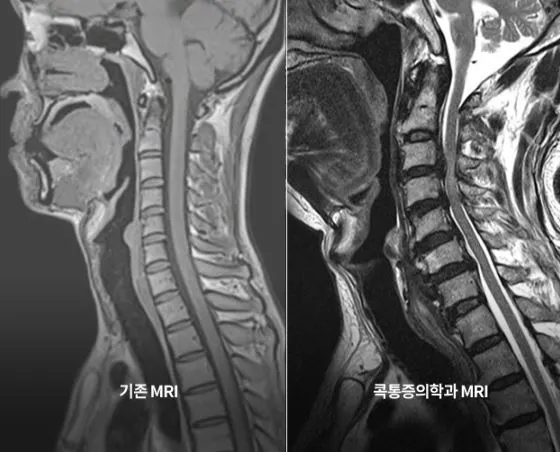

정확한 진단을 위해서는 선명한 영상이 뒷받침되어야 합니다. 즉, 고화질의 MRI 영상을 확인할 수 있는 최신 의료 장비로 MRI 검사를 진행해야 합니다. 단순히 MRI비용 만으로 병원을 선택하는 것보다는 최신식 첨단 장비를 보유하고 있는지, 영상의학과 전문의가 직접 판독하며, 진단뿐 아니라 치료를 시행하는 통증의학과 전문의가 협진이 이루어지는지 고려해봐야 합니다.

콕통증의학과의 MRI 검사

본원은 분당서울대병원과 동일한 지멘스의 1.5T MRI 기기를 보유하고 있을 뿐만 아니라 MRI 촬영이 필수적인지 사전에 검토하여 필요한 경우에만 촬영하도록 함으로써 환자의 부담을 덜어드릴 수 있도록 노력하며, 근골격계 영상전문의가 판독을 시행하여 대학병원과 동일한 수준의 척추관절 검진시스템을 가지고 있습니다.